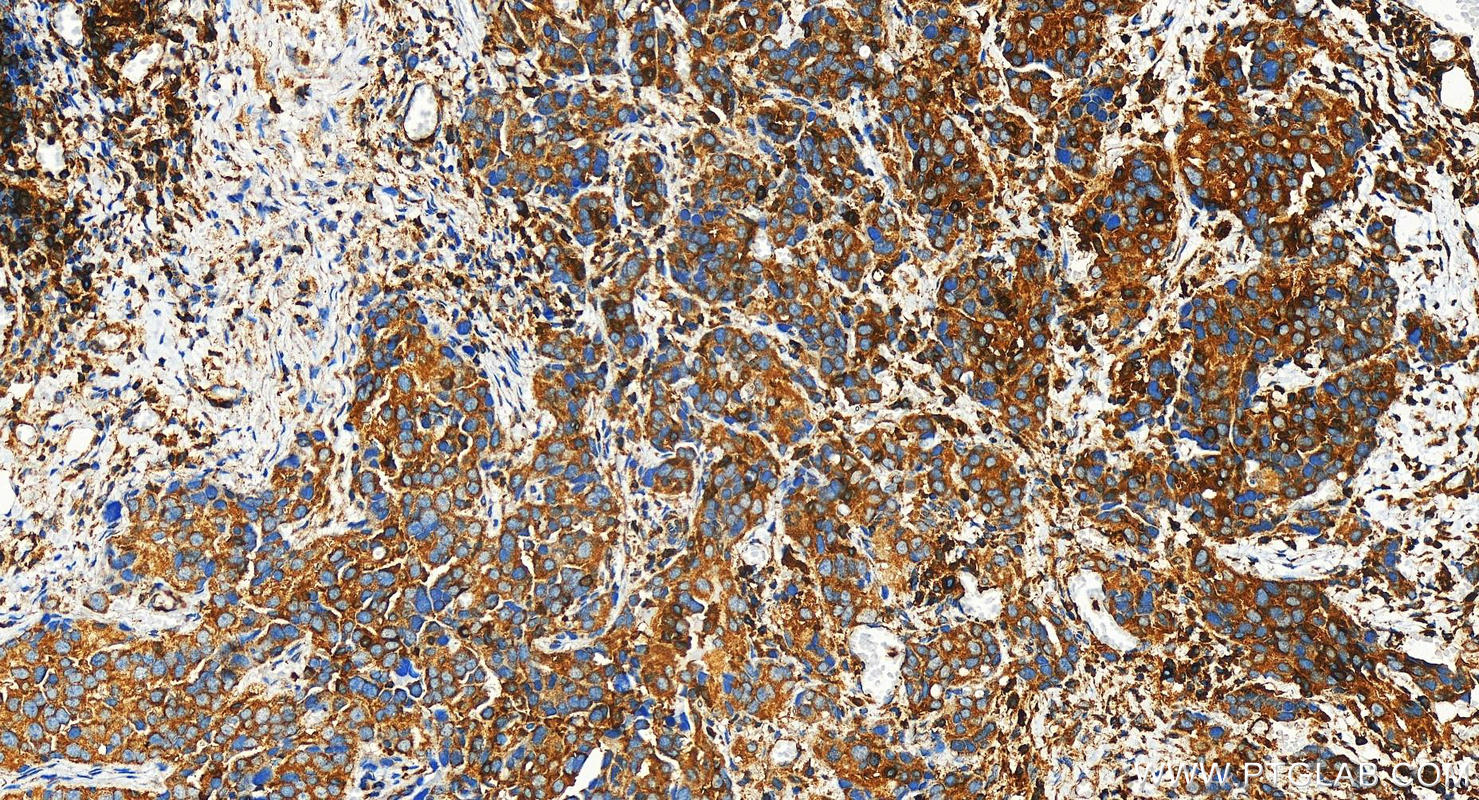

| Positive IHC detected in | human ovary cancer tissue Note: suggested antigen retrieval with TE buffer pH 9.0; (*) Alternatively, antigen retrieval may be performed with citrate buffer pH 6.0 |

| Immunohistochemistry (IHC) | IHC : 1:250-1:1000 |